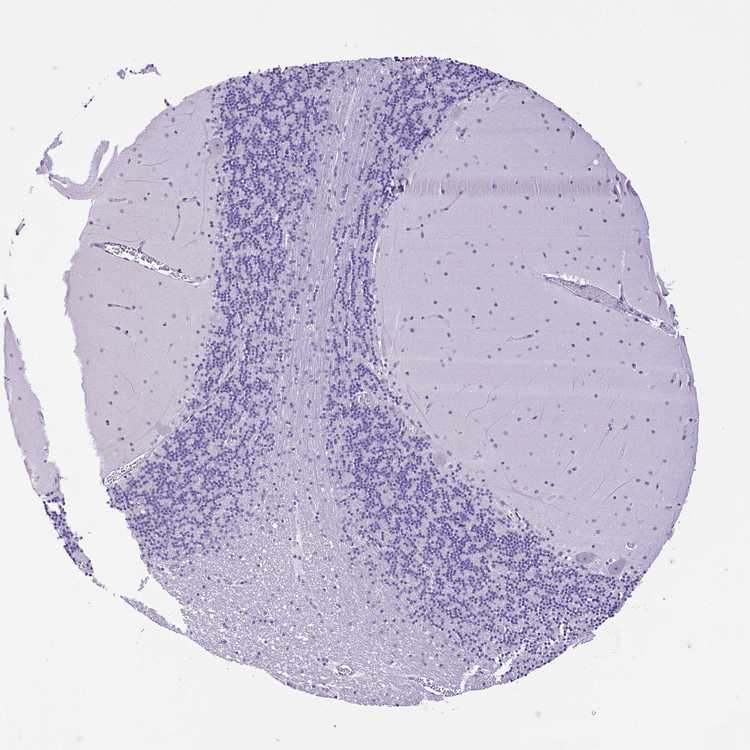

BRAIN CEREBELLUM Show tissue menu

CEREBELLUM - Expression summary

CEREBELLUM - Antibody stainingi

Antibody staining in the annotated cell types in the current human tissue is reported as not detected, low, medium, or high, based on conventional immunohistochemistry profiling in selected tissues. This score is based on the combination of the staining intensity and fraction of stained cells.

Each image is clickable and will lead to virtual microscopy that enables deeper exploration of all samples and also displays staining intensity scores, fraction scores and subcellular localization as well as patient and tissue information for each sample.

Antibody HPA045064

Purkinje cells Not detected

Cells in granular layer Not detected

Cells in molecular layer Not detected